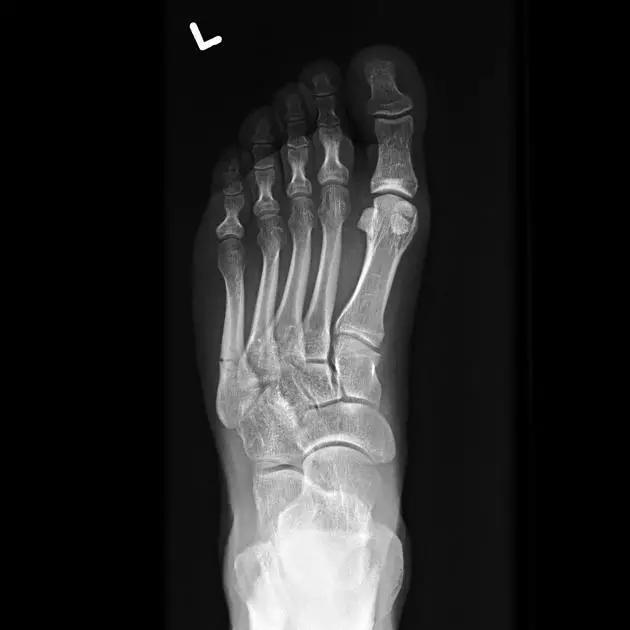

13. Lisfranc 骨折

骨折累及到足的跗骨关节。跖跗关节位于足的前部,是构成足纵弓及横弓的重要结构。

第一跖骨与第一楔骨组成鞍状关节,整个跖跗关节的稳定性,有赖于第一跖跗关节的稳定性,一旦第一跖跗关节发生脱位,其他 4 个跖跗关节容易发生脱位。第一跖跗关节的关节囊有背侧和跖侧副韧带增强,其内缘尚有胫前肌腱附着。第一、二跖骨基部无韧带相连,第一楔骨与第二跖骨基部间有坚韧的 Lisfranc 韧带相连,有助于第一跖跗关节的稳定性。第二楔骨较短,第二跖骨位于第一、二楔骨之间成为外力作用的支点。因此第二跖骨基底易发生骨折。

Lisfranc 关节复合体(Lisfranc joint complex)示意图:first metatarsal 第一跖骨;second metatarsal 第二跖骨;Lisfranc joint 利斯弗朗关节;first,second and third cuneiforms 第一,二,三楔骨;cuboid 骰骨